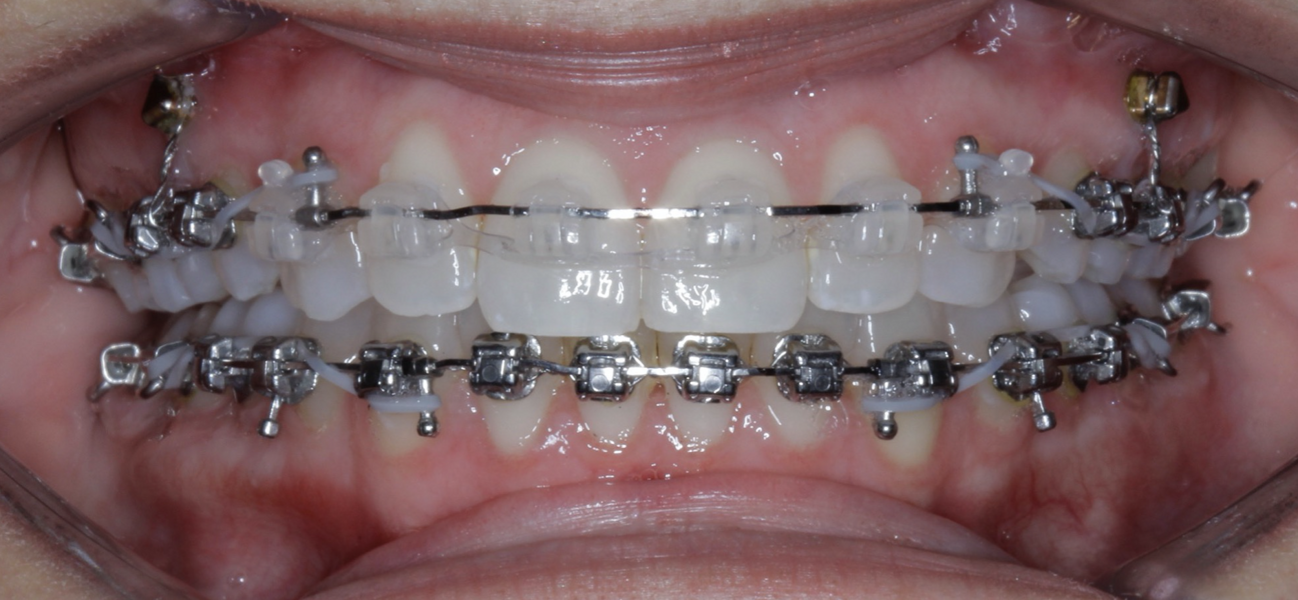

New Age orthodontics and orthopaedics with temporary anchorage devices